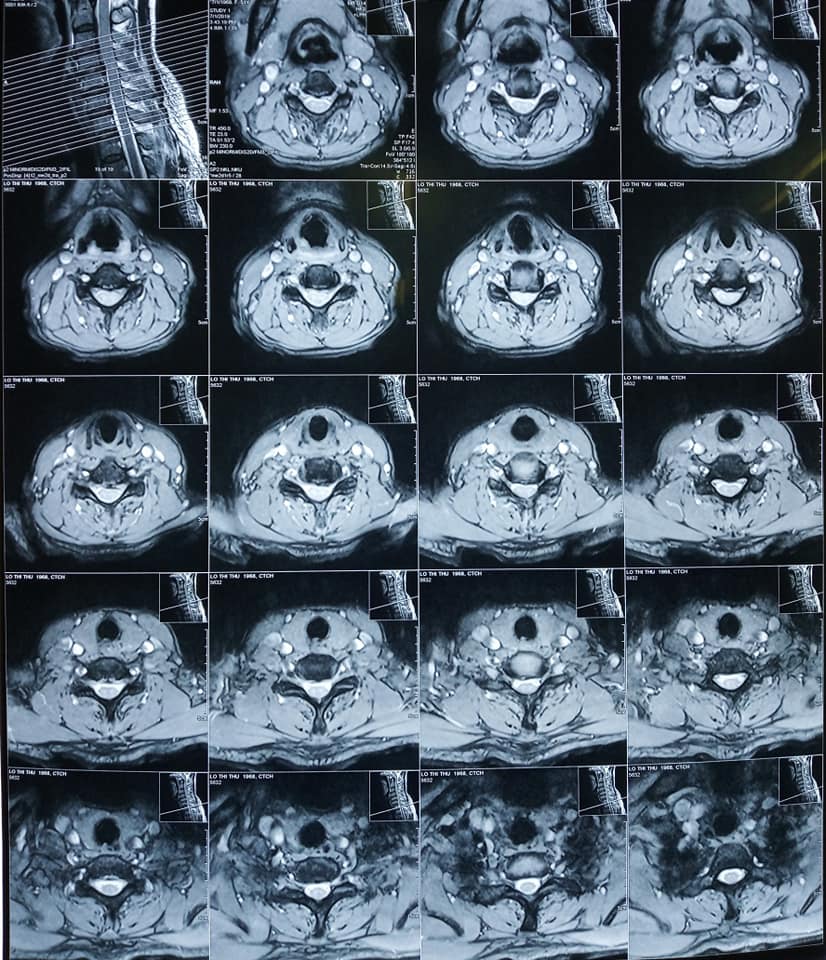

Sau khi được bác sĩ thăm khám, bệnh nhân được chẩn đoán bị Thasit vị đĩa đệm cột sống cổ C4C5 C5C6 và phù tủy cổ ngang mức C5.

Hình ảnh Phim chụp tình trạng :